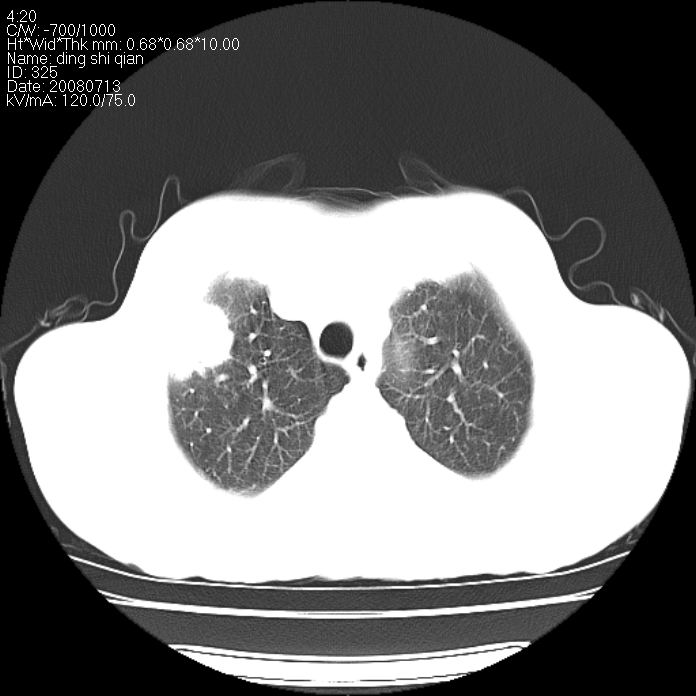

标题: CT14654:男 50岁 近来胸痛 [打印本页]

标题: CT14654:男 50岁 近来胸痛

周围性肺ca

非常残酷:肺癌!

周围型肺癌。

肺癌

周围性肺癌